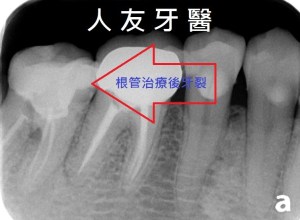

由上面那張照片我們可以清楚的看到不管是金屬牙套或內冠金屬外面燒瓷牙套都會釋放金屬離子 , 久了會造成牙齒與牙齦交接處黑黑的 , 因為模型有熱脹冷縮的關係 , 所以牙套本身也與自己的牙齒不是那麼密合 , 易從縫隙蛀進去 ; 而數位全鋯牙套 , 因牙套本身不含金屬材質所以不會有牙套釋放金屬離子的問題 , 牙齒與牙齦交接觸自然也不會黑黑的 , 因是數位取模 ,所以電腦設計精密度高 , 密合度自然也就比較好 .